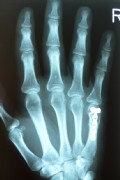

Fracture of the fifth metacarpal bone.

This young man fell off the skateboard and broke his fifth metacarpal. The conducted cast immobilization in the emergency hospital was found to be ineffective, because the bone was flexed too much.

After the straightening and plating the injury healed very well.